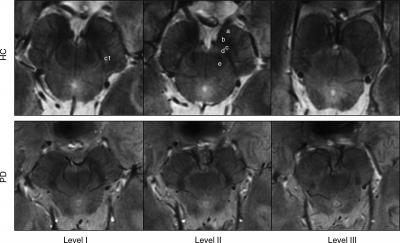

Using the 7-T MRI, the researchers were able to distinguish a three-layered organization of the substantia nigra (SN), a crescent-shaped mass of cells in the midbrain. Parkinson's disease results from the loss of dopamine-producing cells located in this region of the brain. Dopamine is an important neurotransmitter involved in multiple brain functions, including motor and behavioral processes such as mood, reward, addiction and stress.

Based on abnormalities in the SN identified by the 7-T MRI, the researchers correctly classified patients with Parkinson's disease with a sensitivity of 100 percent and specificity of 96.2 percent.